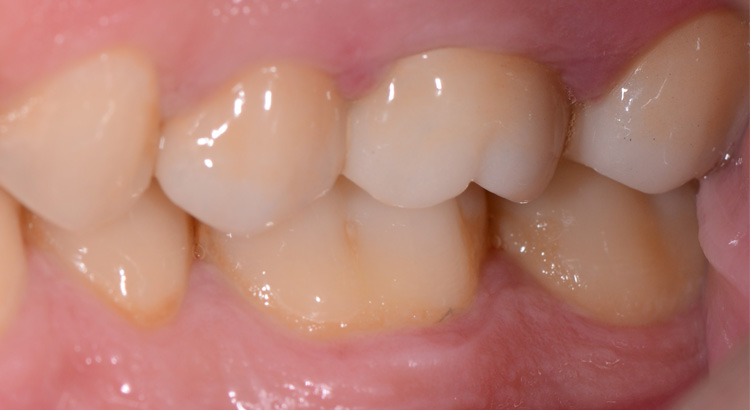

Protesi fissa su denti naturali

Il paziente presentava carie su tutti e tre gli elementi del settore posteriore, fondamentali per una corretta masticazione. La carie aveva portato ad una grave compromissione degli elementi, dolore dentale e il paziente masticava solo dall’altro lato. Grazie al trattamento endodontico e l’utilizzo delle nuove ceramiche è stato possibile ristabilire l’estetica e soprattutto la funzione masticatoria di quel lato.